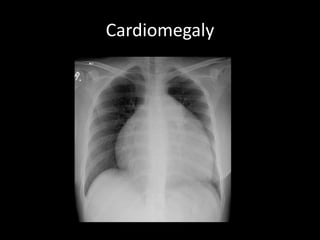

Cardiomegaly